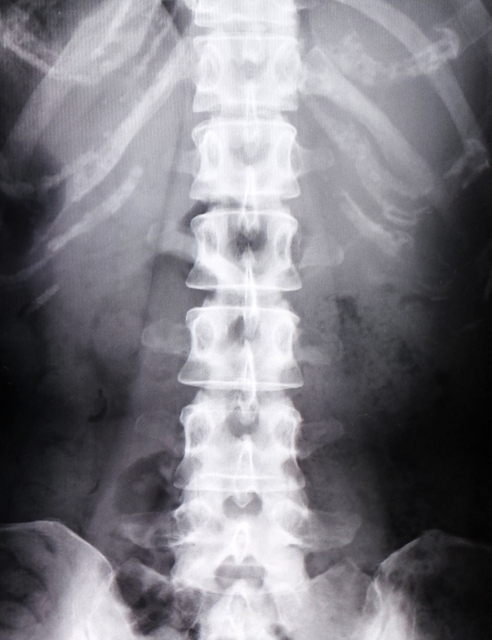

それなら整形外科、と受診してみるとレントゲンやMRI検査の結果から、「特に異常はないね」「背骨のすき間が少し狭いね」などと言われることが多いです。